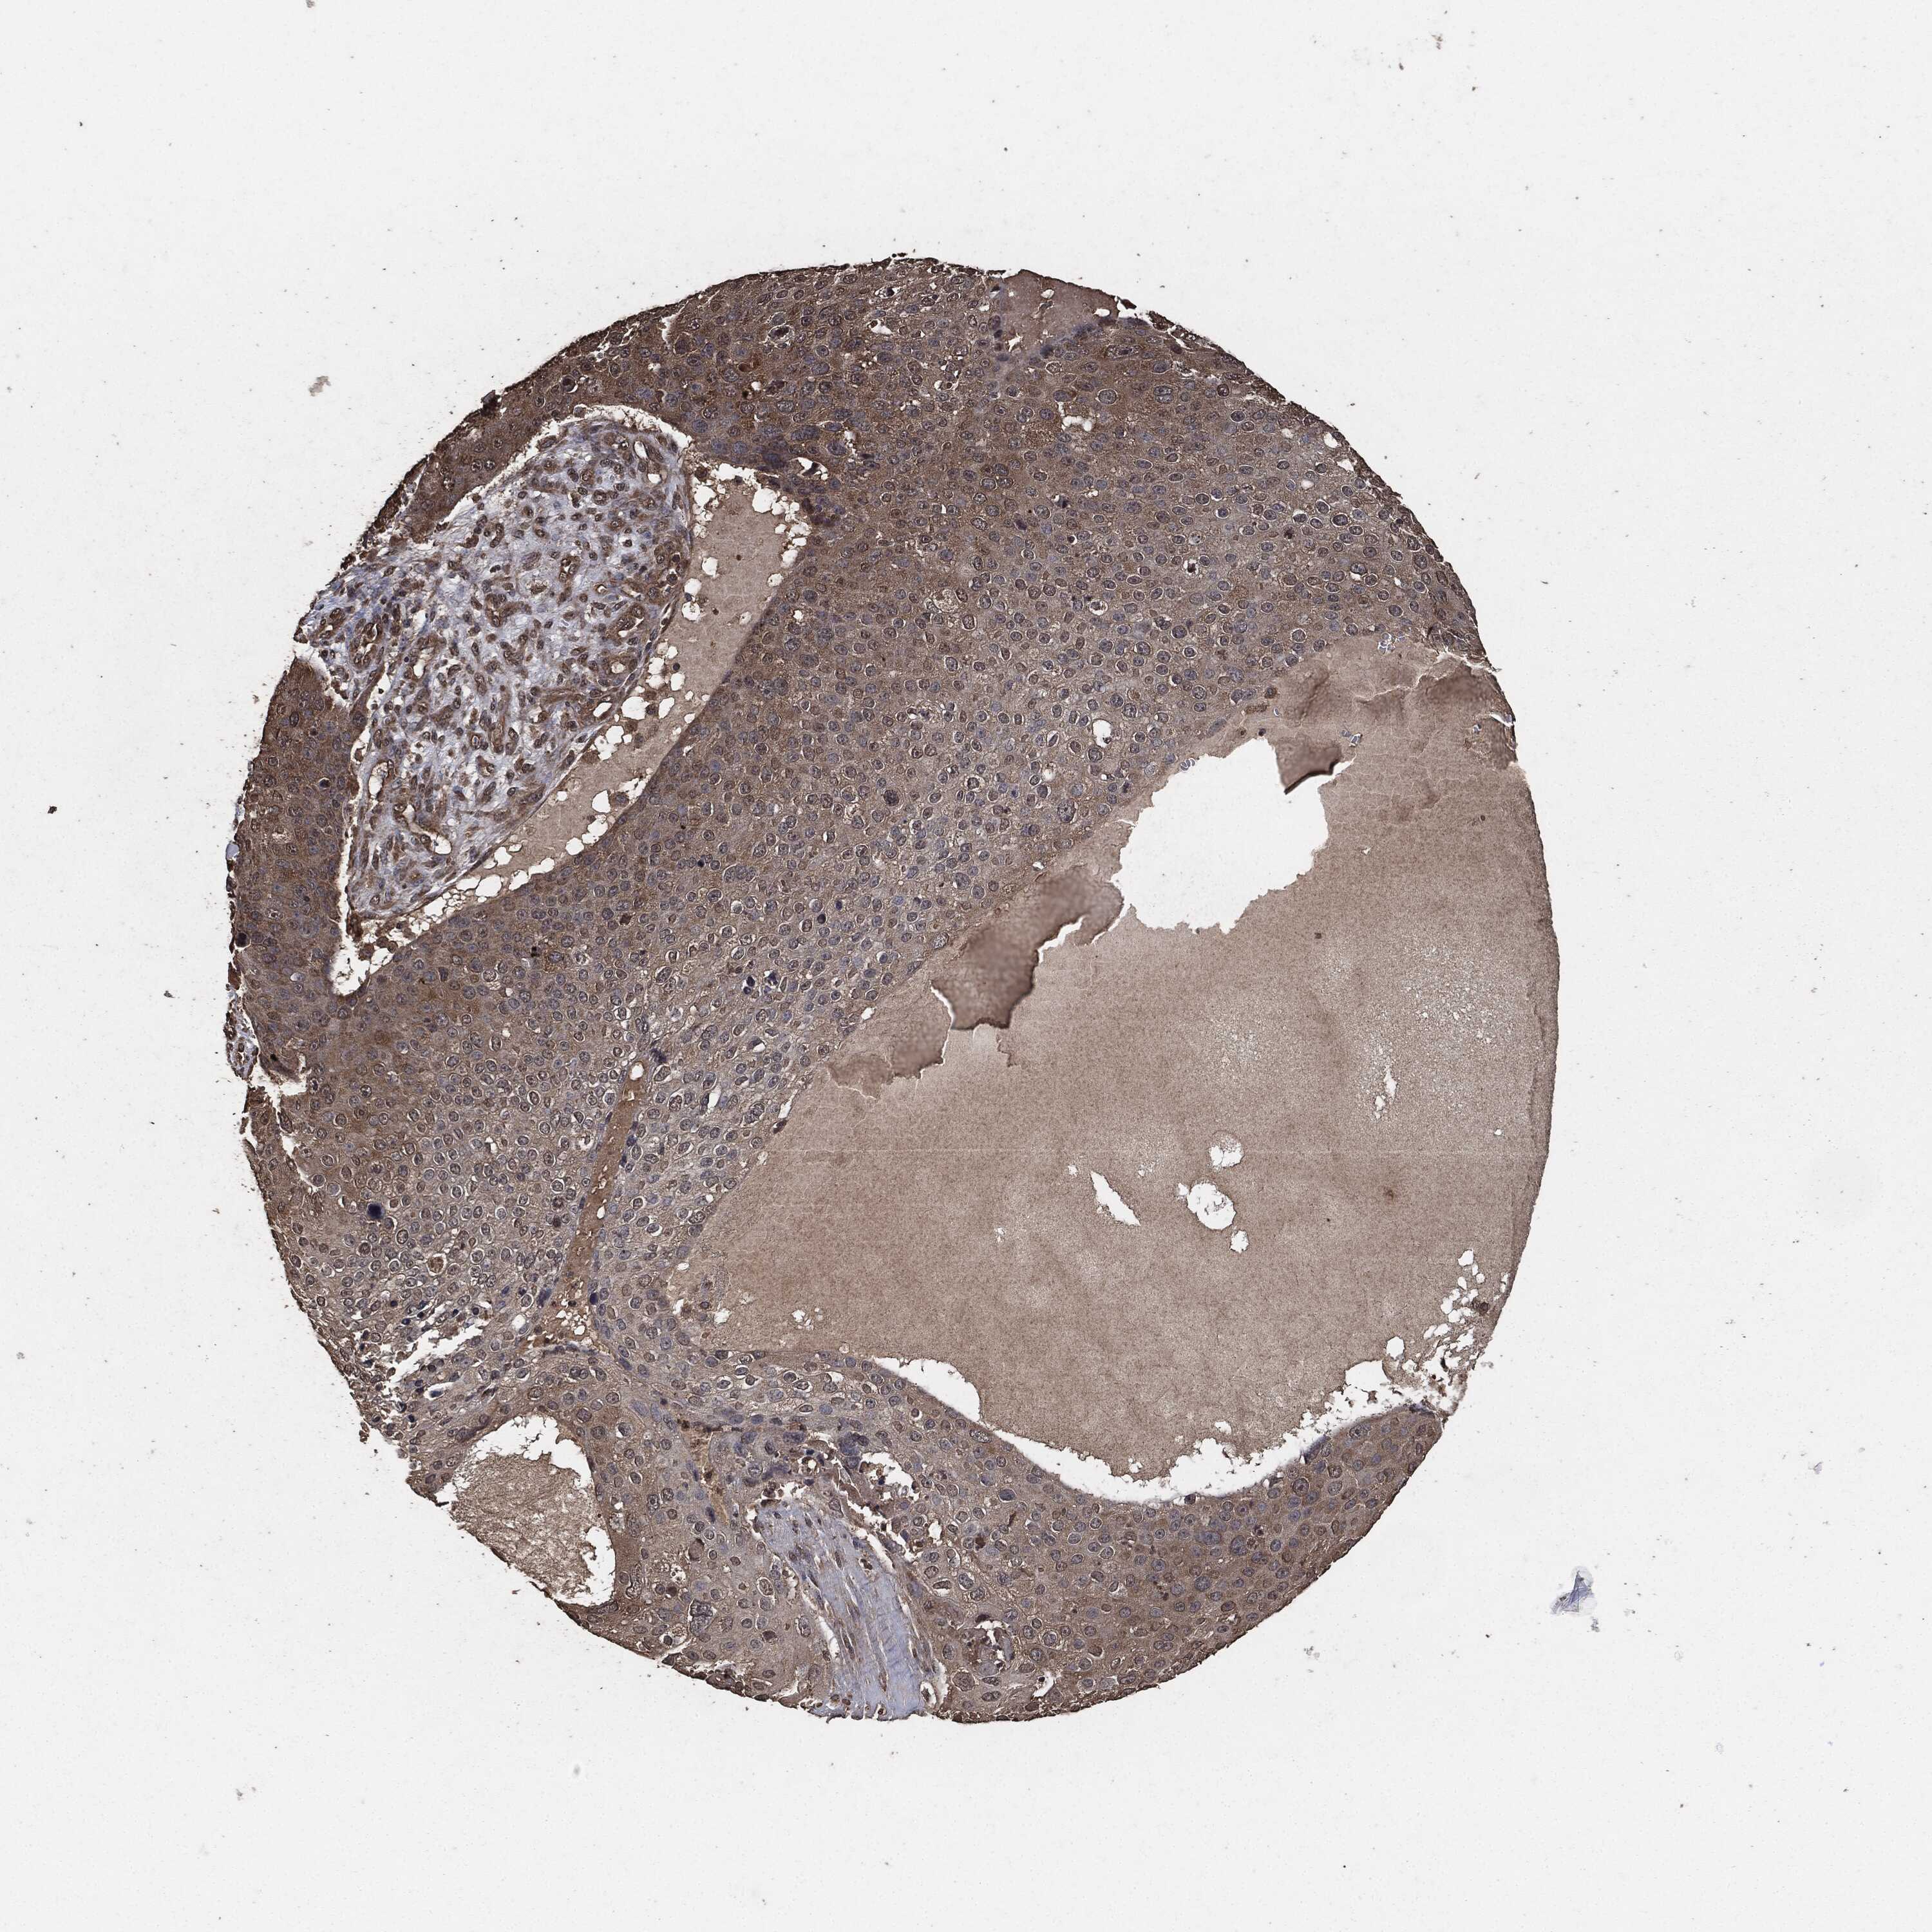

SKIN CANCER - Protein expressioni

A mouse-over function shows sample information and annotation data. Click on an image to view it in a full screen mode. Samples can be filtered based on level of antibody staining by selecting one or several of the following categories: high, medium, low and not detected. The assay and annotation is described here.

Each image is clickable and will lead to virtual microscopy that enables deeper exploration of all samples and also displays staining intensity scores, fraction scores and subcellular localization as well as patient and tissue information for each sample.

Antibody CAB021903

Staining

High

Medium

Low

Not detected

Intensity

Strong

Moderate

Weak

Negative

Location

Nuclear

Cytoplasmic/membranous

Cytoplasmic/membranous,nuclear

None

Basal cell carcinoma

BCC, high aggressive

Squamous cell carcinoma, NOS